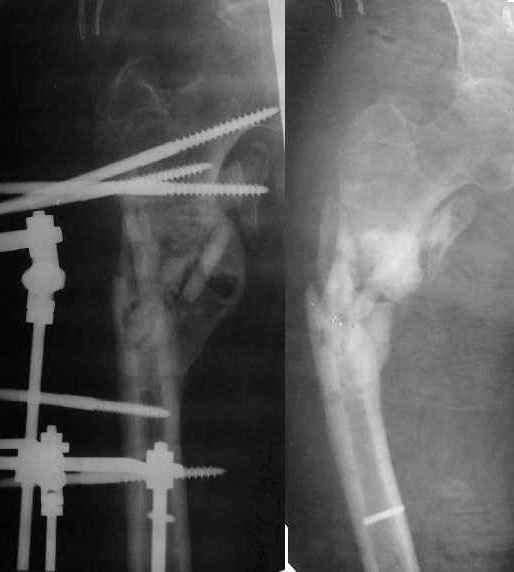

Более года назад пациент был оперирован в одном из НИИТО. При контрольном осмотре через год: болевой синдром, контрактура в локтевом суставе, патолгическая подвижность нижней трети плеча